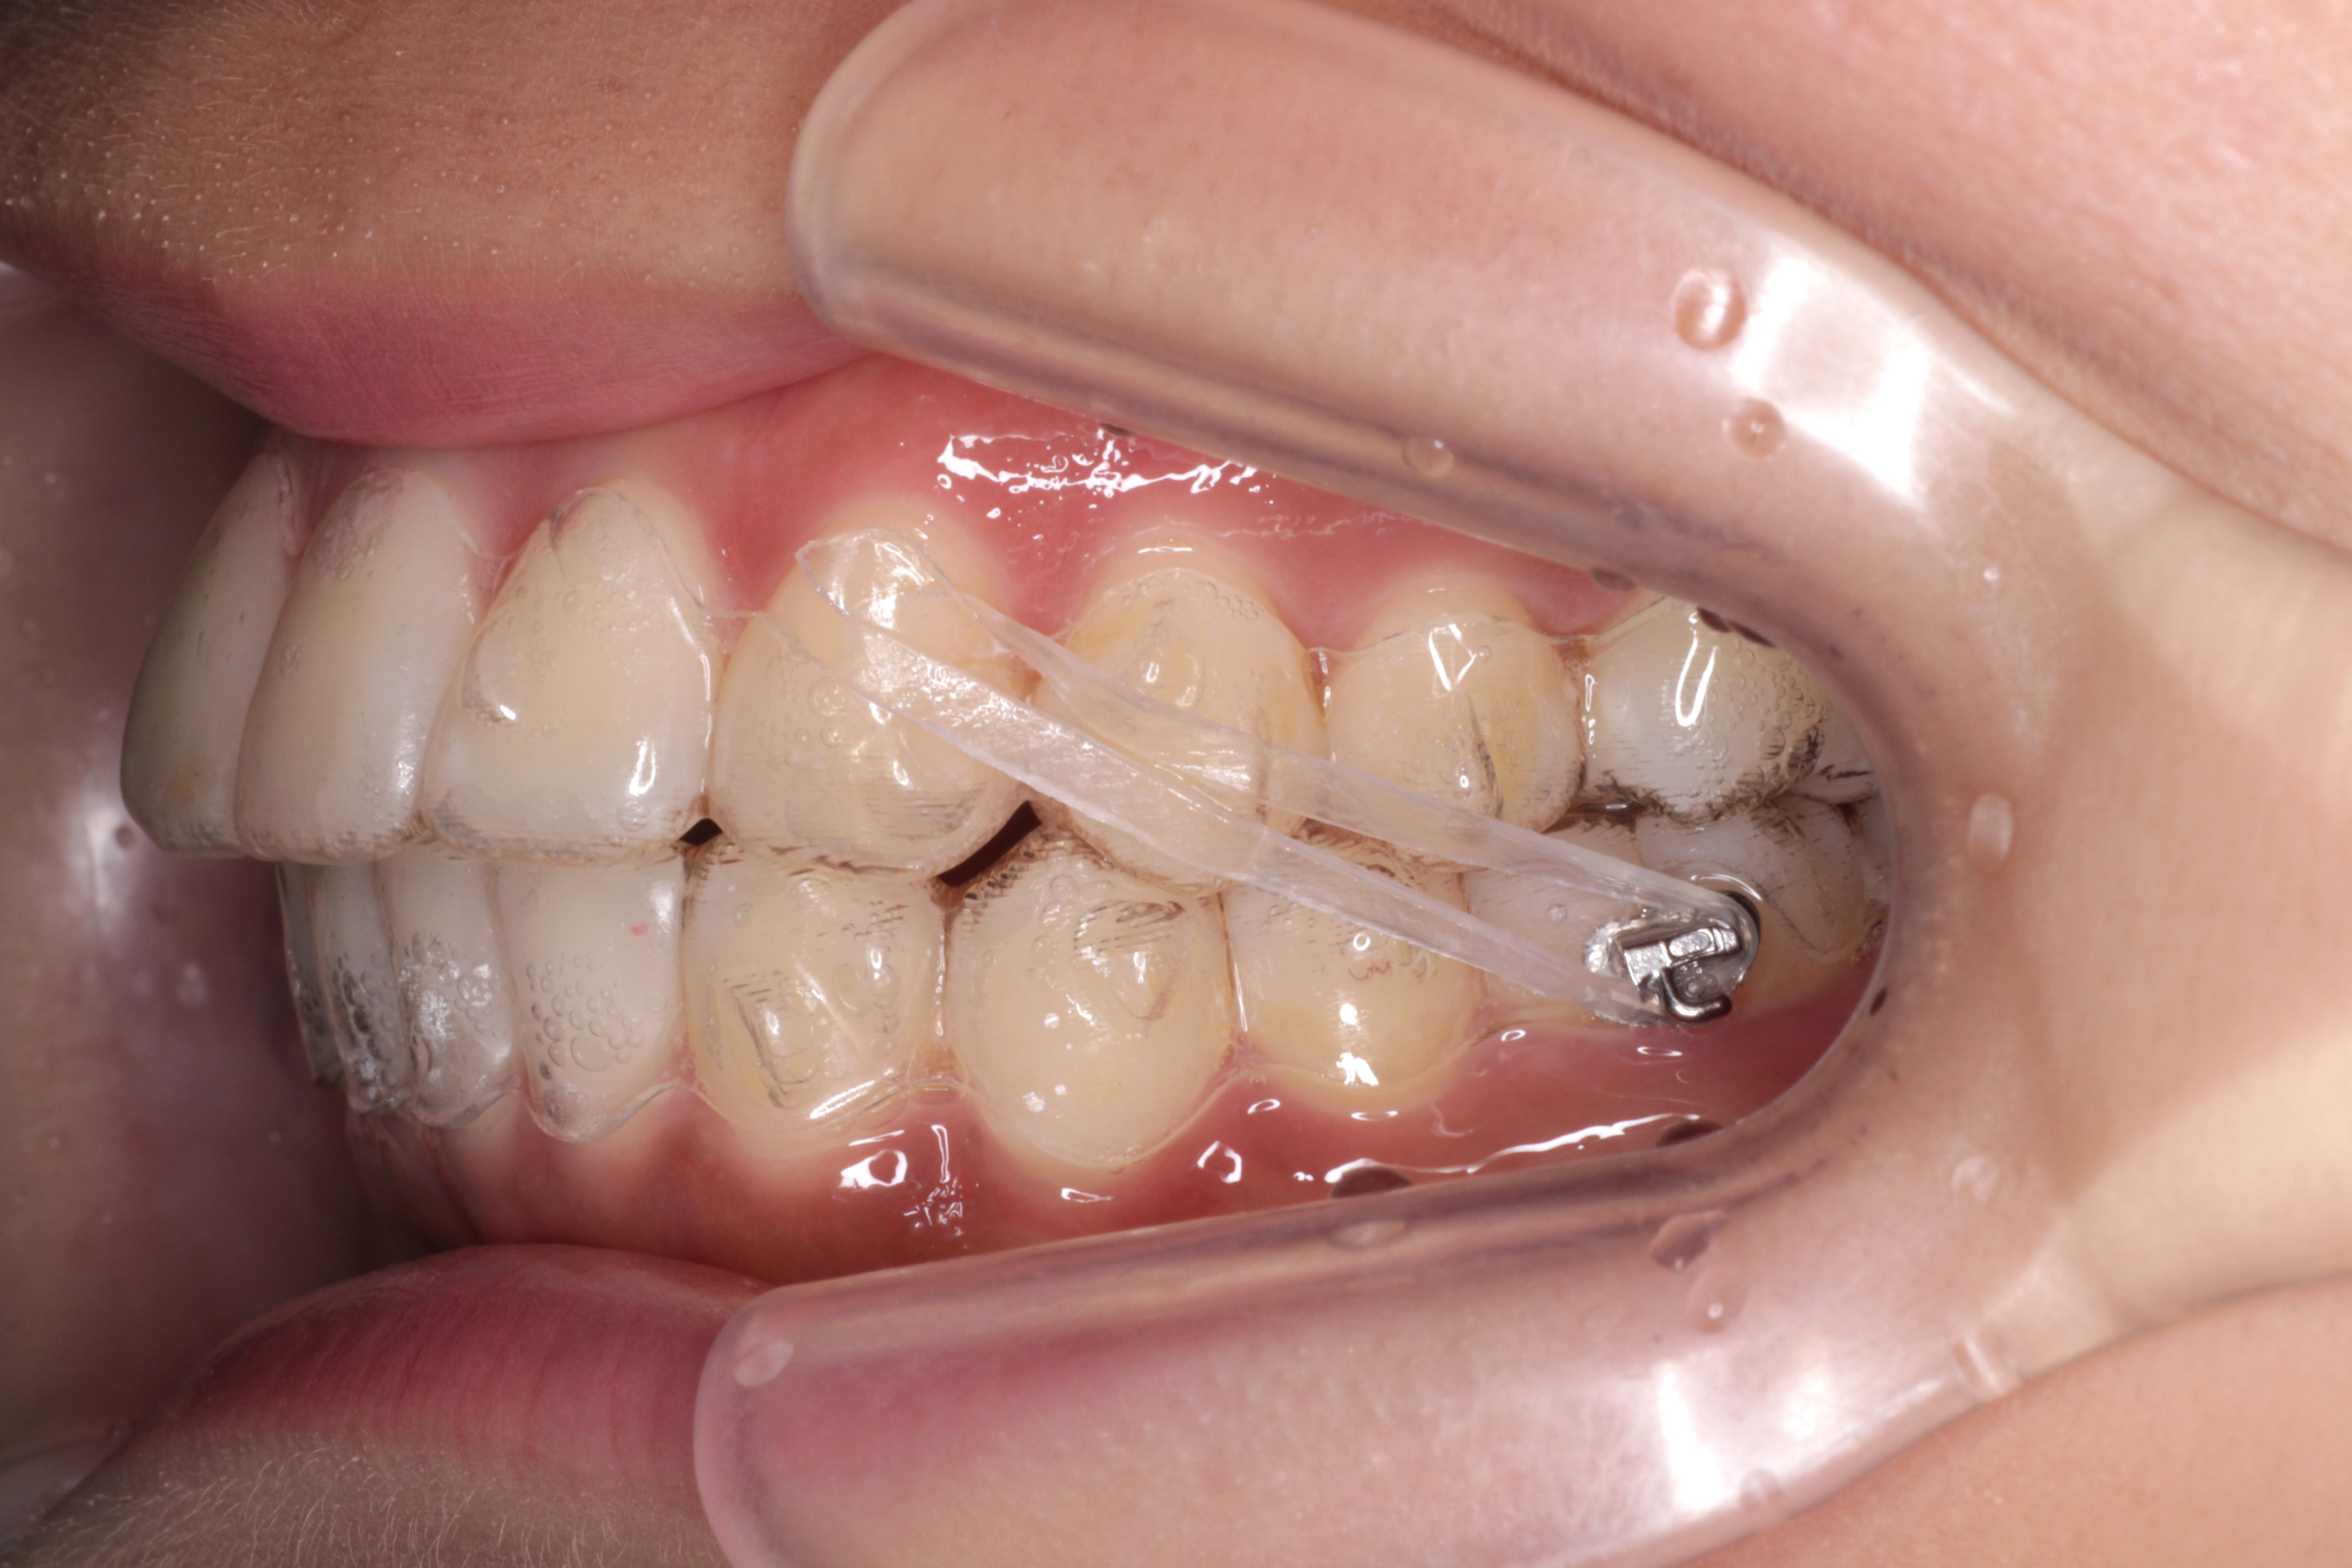

インビザラインでゴムかけする場合は、写真のような方法でゴムかけをします。

(こちらの写真は当院スタッフの口腔内です)

下の奥歯にボタン(ゴムをかける為のフック)をつけ固定します。

上のマウスピースはゴムがかけられるような仕組みになっているので

下のボタンと上のマウスピースにゴムをかける事で遠心力で上の奥歯を後ろにさげます。